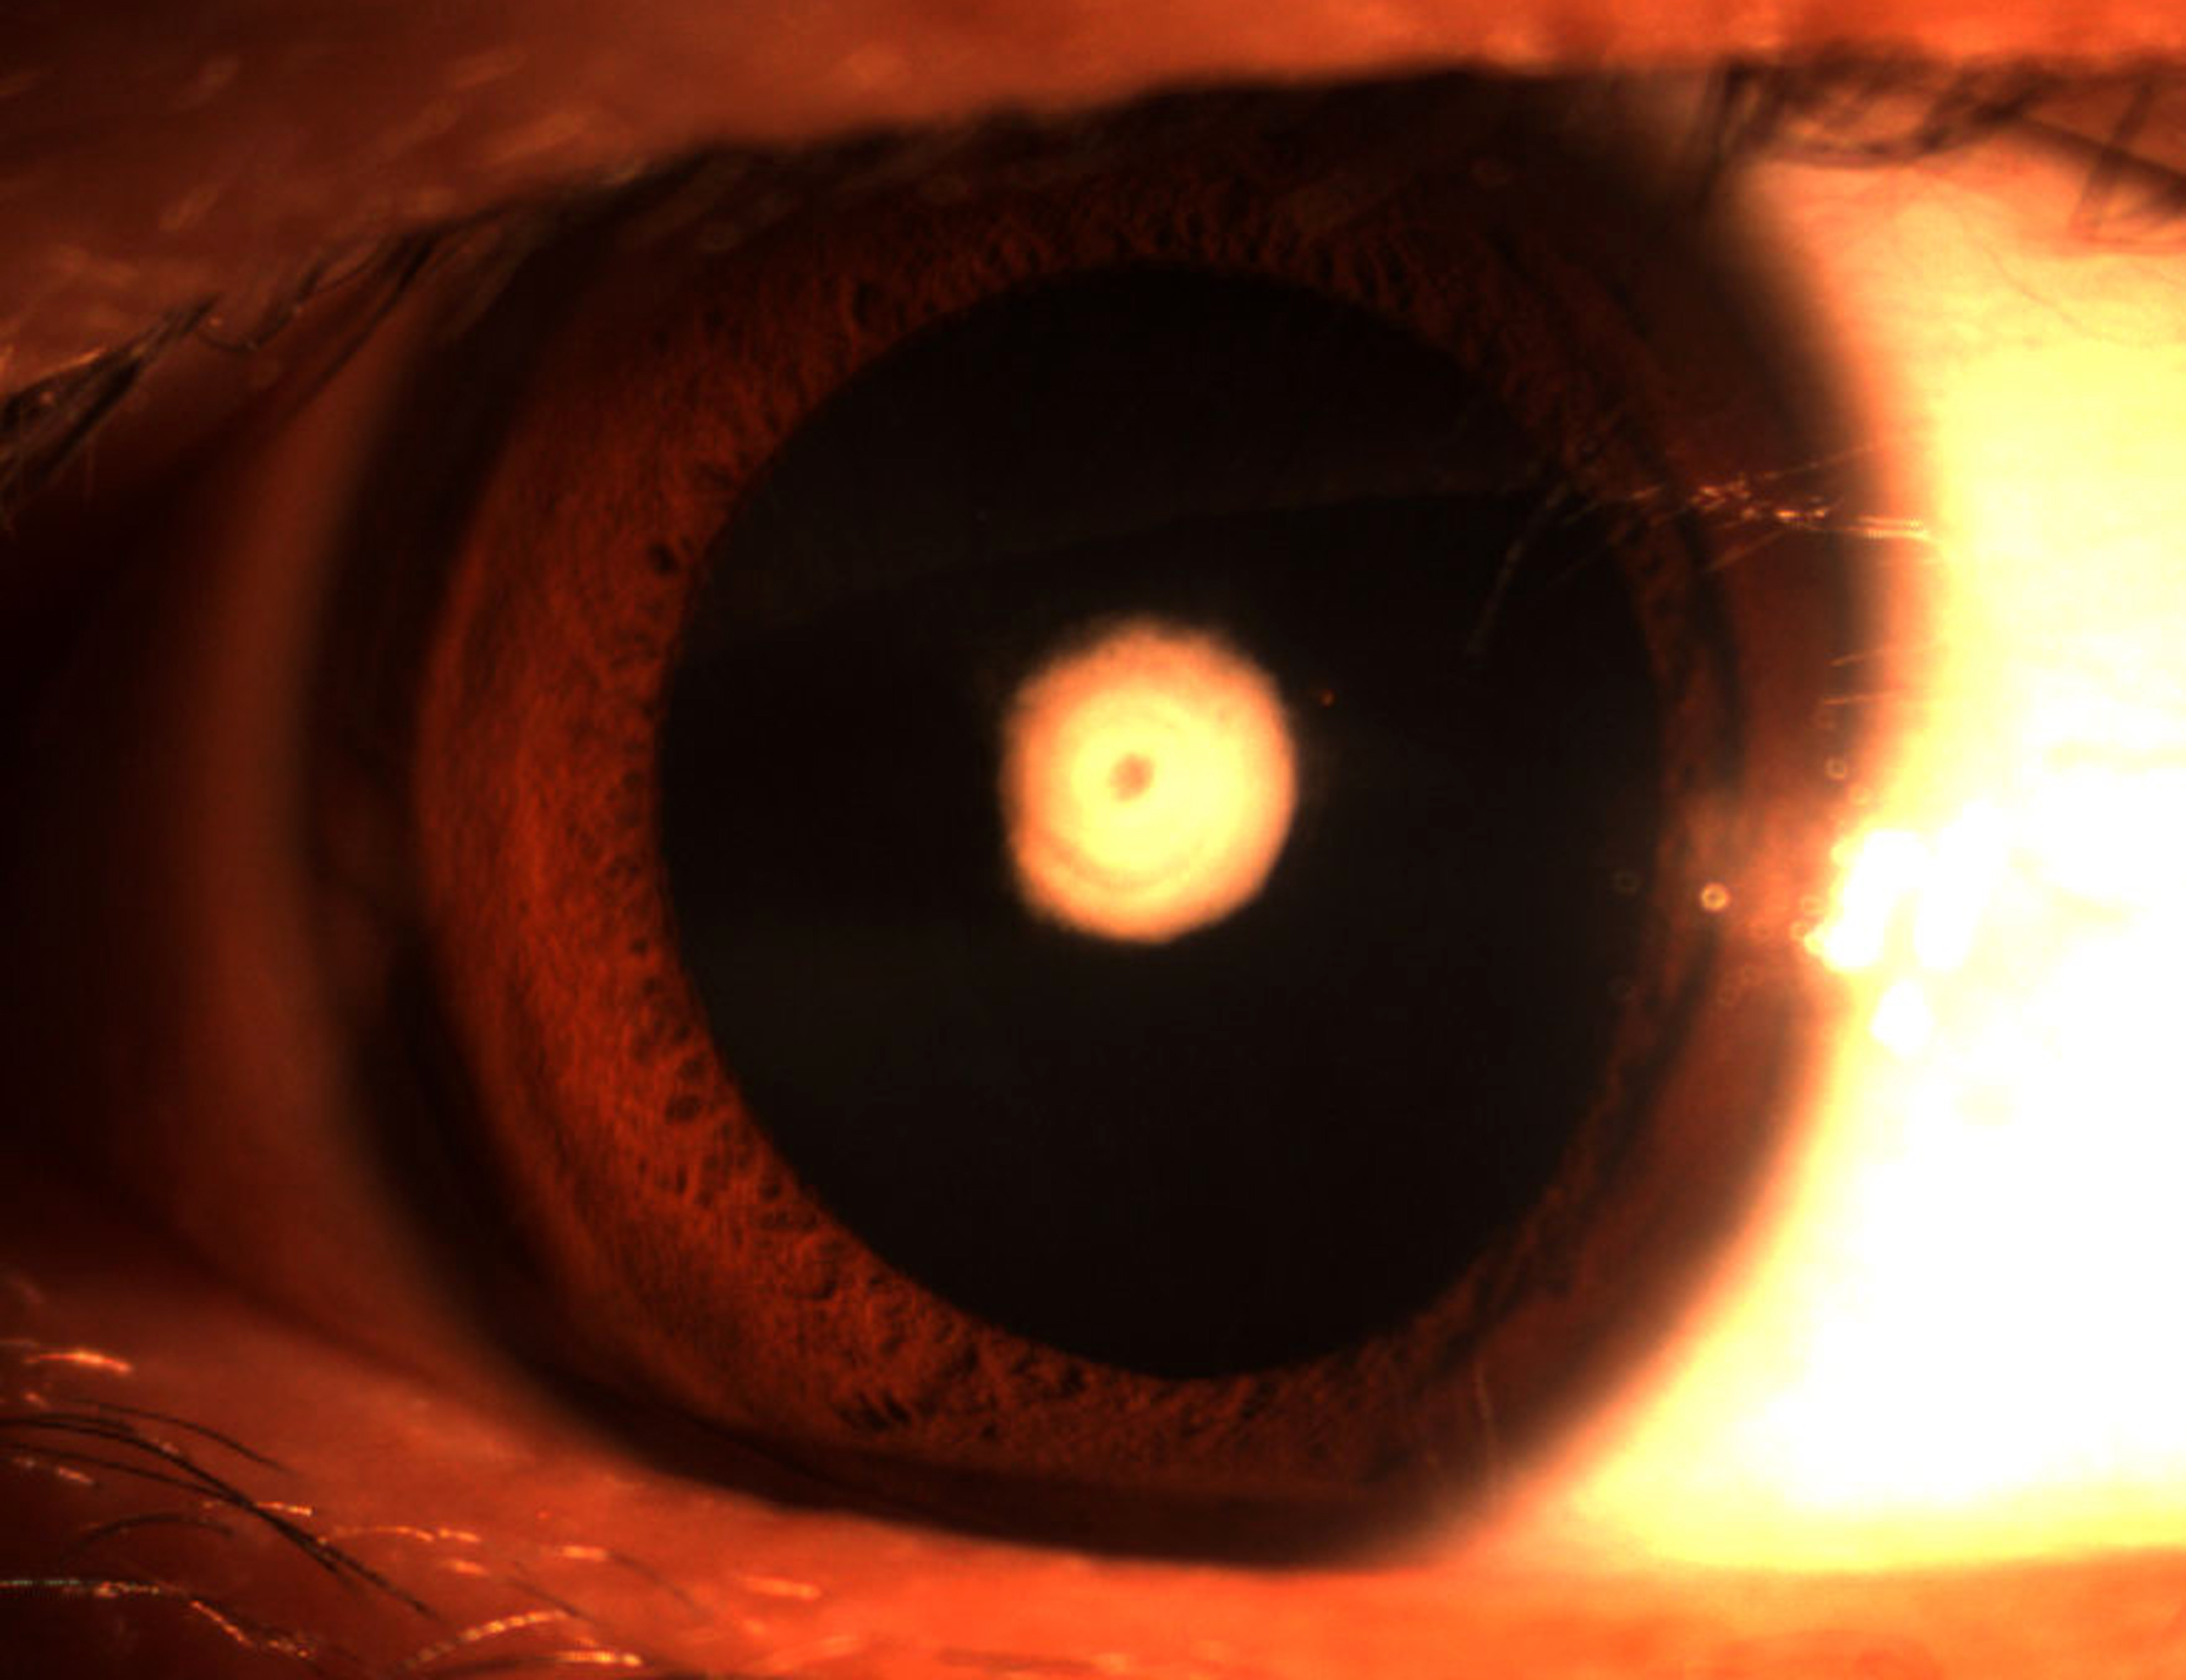

Figure 2 of Wang, Mol Vis 2012; 18:968-973.

Figure 2. Slit lamp photographs of the proband. The photograph of the proband (III: 2) shows nuclear opacities of the lens involving embryonal nucleus.